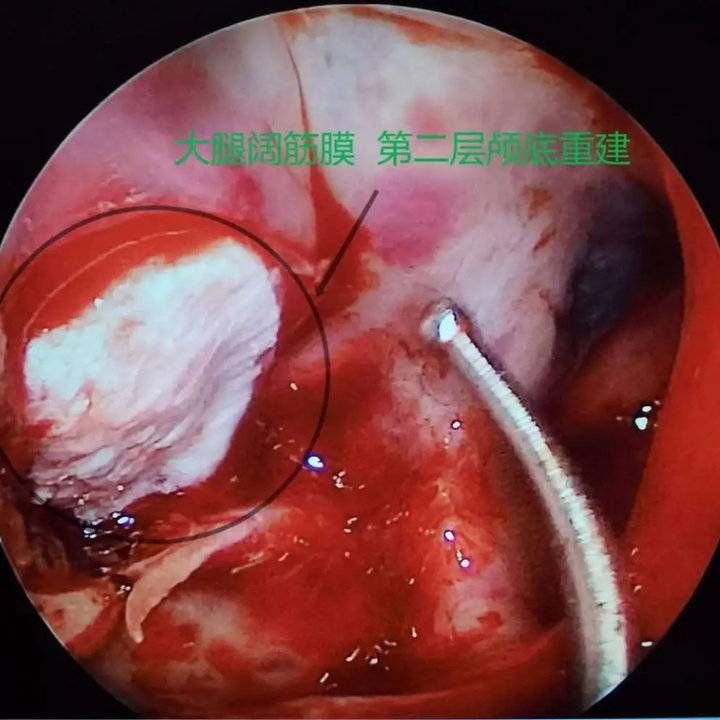

经呼吸科、麻醉科、耳鼻喉科及重症医学科评估后,8月4日,赵秋良主任团队为患者进行了鼻内镜下脑膜脑膨出切除+脑脊液修补+颅底重建手术。赵秋良主任介绍,这是全市首例鼻内镜下脑脊液修补手术,是鼻科鼻内镜微创手术里难度系数最高的四级手术之一,该手术充分利用人体自然腔道,全程在高清屏幕直视下完成,创伤小、愈后良好,术后并发症少,脑脊液修复的成功率高达90%。